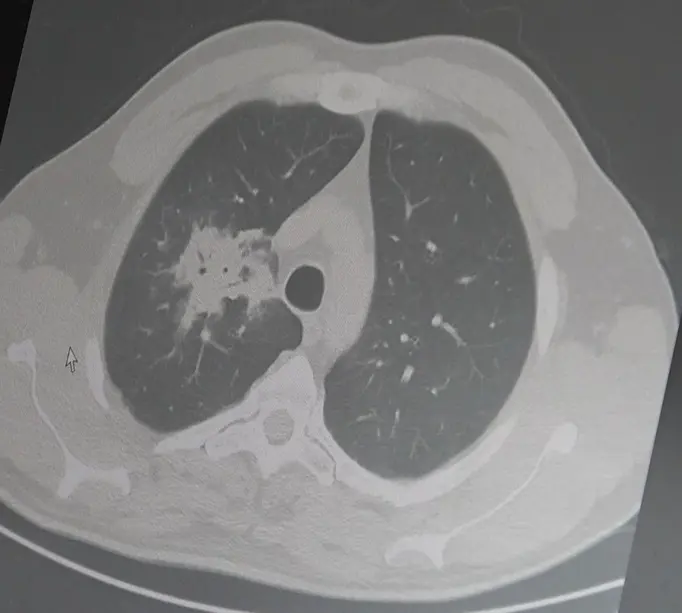

Akciğer kanseri geç fark ediliyor: Hastaların yüzde 60'ında kanser ileri evrede tespit ediliyor